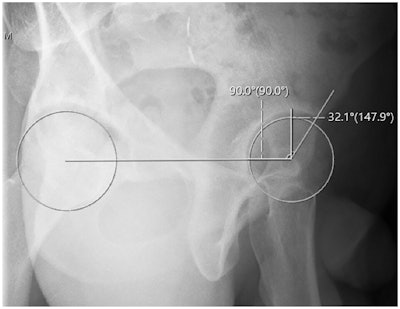

In this study, the team investigated whether their novel method, which uses standard x-ray viewing tools to generate a true horizontal reference line and best-fit circles on each femoral head, may allow for more precise assessments.

Anterior center edge angle measurement utilizing a horizontal reference line. Orthopedic Journal of Sports Medicine

The traditional ACEA measurement technique involves drawing a vertical ray from the center of the femoral head parallel to the lateral margin of the x-ray, followed by an intersecting ray from the center of the femoral head to the lateral margin of the acetabular sourcil. However, this measurement is greatly dependent on patient positioning and imaging technique, the group noted.